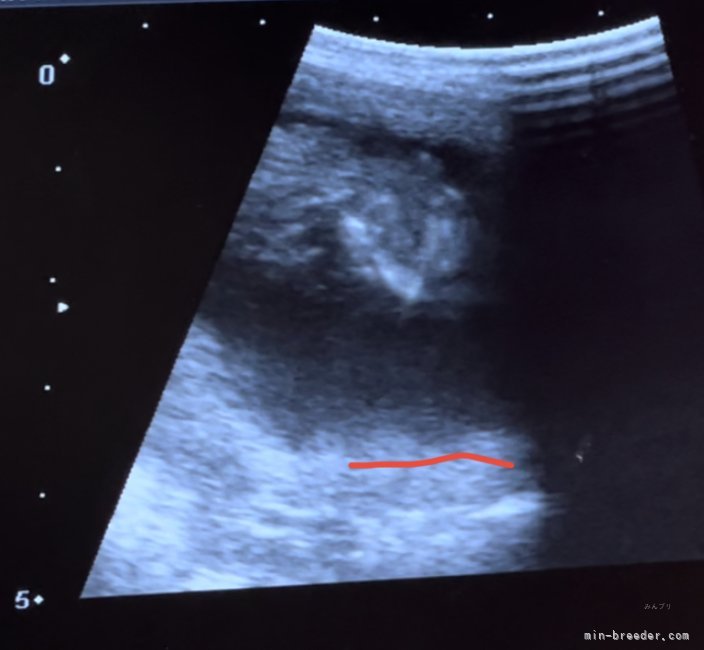

エリザベス(2回目)9月20日頃

リッツ(初産)9月20日頃

ピーチ姫(初産)9月25日頃

クリス10月上旬

アクアマリン10月上旬

ブラックダイヤ10月上旬